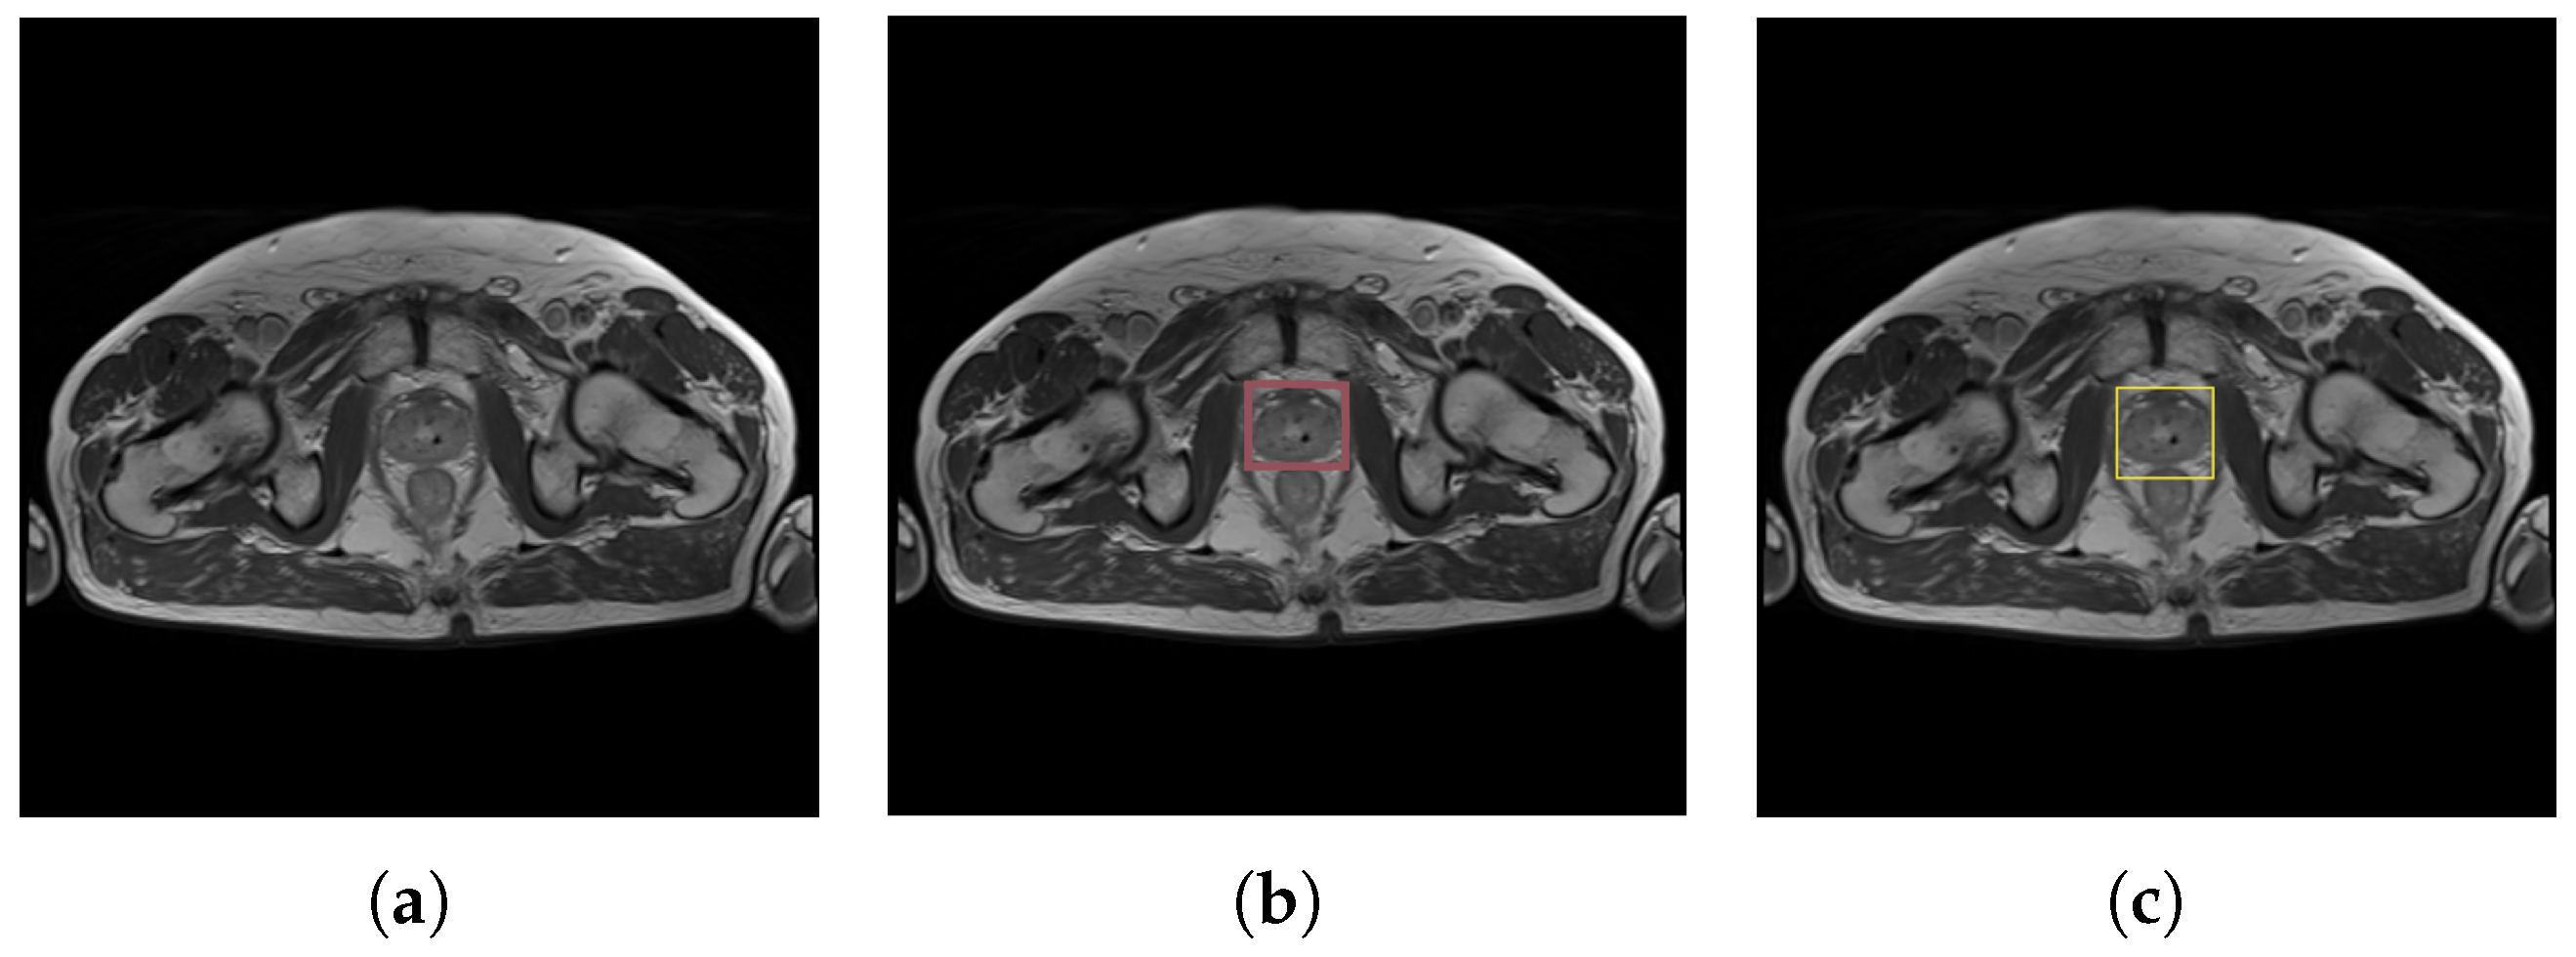

- Onefold modality (MRI)—The first experiment examined the performance of a model trained only on an MRI dataset. The dataset contains 666 training and 73 validation images. In Figure 6, the example validation image compares the predicted bounding box with the ground truth bounding box on the example validation image.

Figure 6. MRI results for prostate detection: (a) original prostate image, (b) ground truth bounding box, and (c) predicted bounding box. - Multimodal medical imagining (MRI and CT)—The training dataset was enlarged by adding CT scans. This approach was used to verify whether generalization is appropriately fitted to varying MRI data. The second experiment was based on 739 MR and 751 CT mixed images, where the validation dataset totals 149 images.